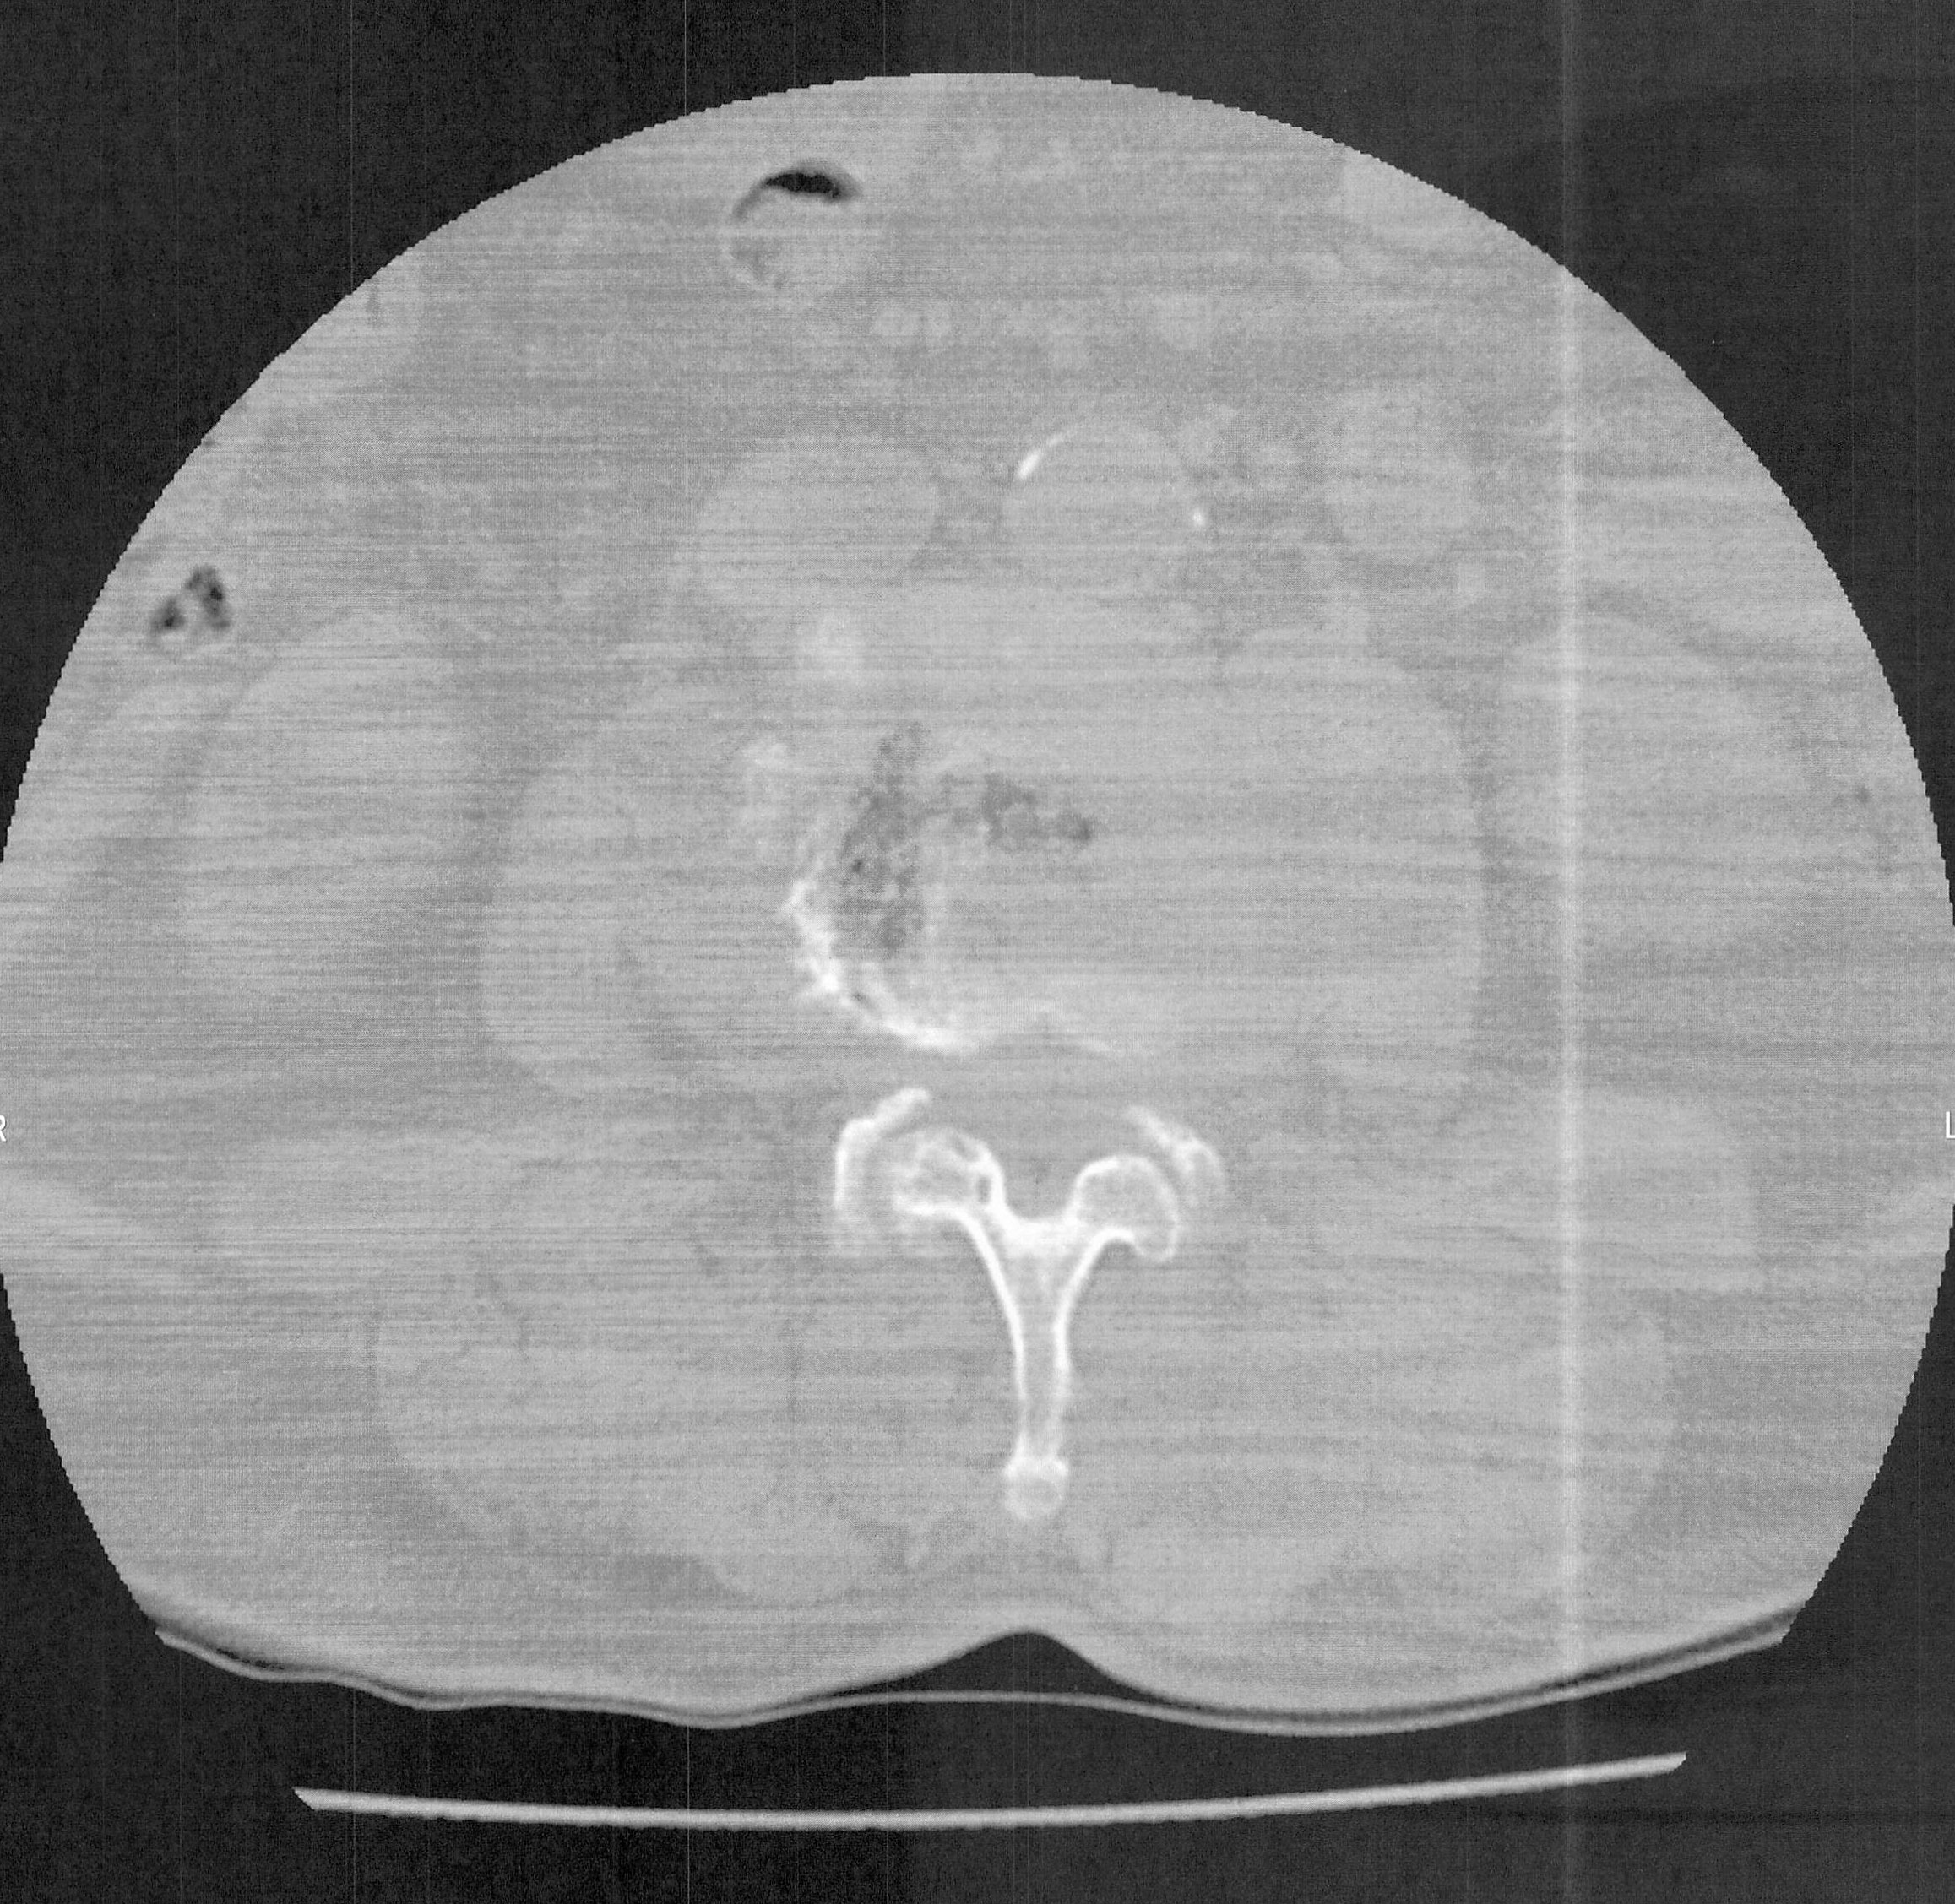

造影剤注入レントゲン検査の結果の画像は③の通りで、2か所の脊柱で造影剤が下に流れていないため、写つていないとのことで、ここで脊柱

管が特に狭窄状態をおこしているとの説明を受ける。